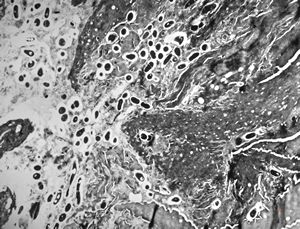

M, 28y. | leishmaniosis … skin of the cheek

M, 28y. | leishmaniosis … skin of the cheek